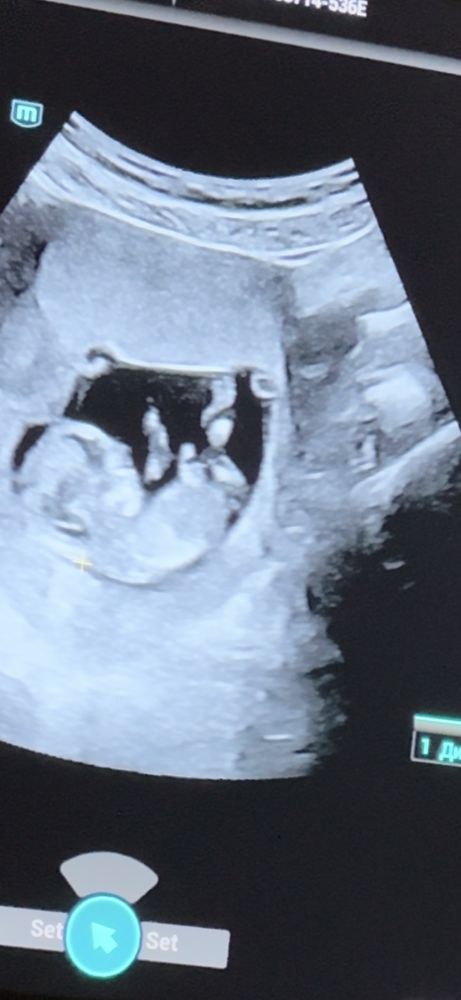

Определение пола

Фото не то, где смотрят пол)) Не знаю кто там ходит к слепым узистам, все видно хорошо на сроке 12 недель. Мне даже в ЖК сегодня сказали что девочка.

Жанна, именно на этом узи мне сказали, что на этом сроке можно ошибиться. В пц на скрининге сказали что бугорок как у девочки. Сб с самого начала 164, потом 172.

Жанна, это скрин с видео которого я записала с монитора. На фото не видно ничего.

Пока непонятно, но больше склоняюсь к мальчику

Екатерина, одна не сказала, говорит можно ошибиться. Вторая говорит, что бугорок как у девочки.